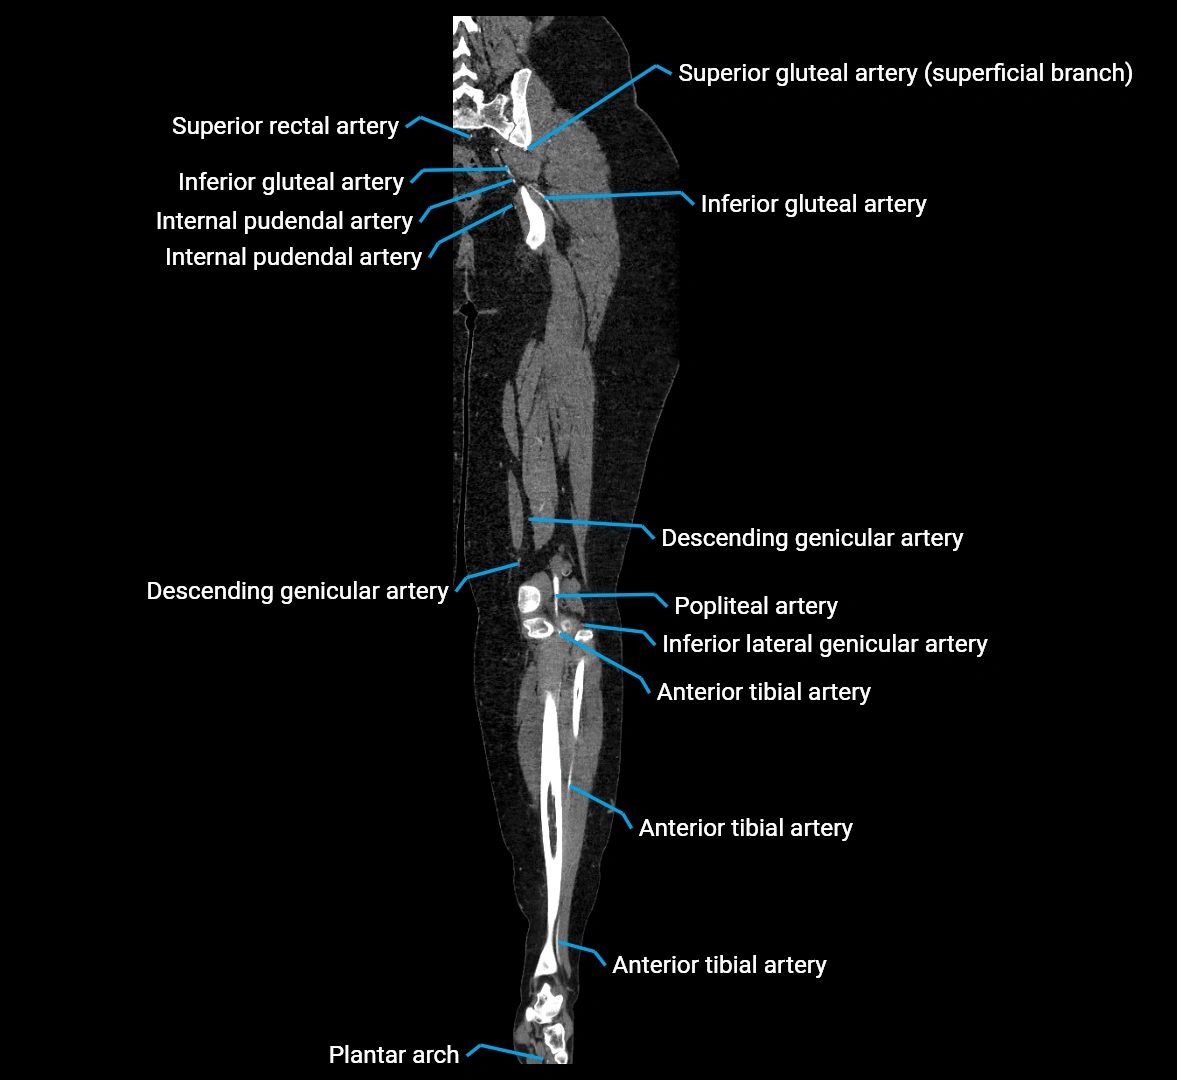

Contrast-enhanced CT (CTA):

• Gold standard for abdominal aortic imaging

• Provides excellent detail of lumen, wall, aneurysm, thrombus, and branch vessels

• Multiplanar and 3D reconstructions help in aneurysm measurement, stent graft planning, and dissection evaluation

• Detects acute rupture, traumatic injury, or occlusion with high sensitivity